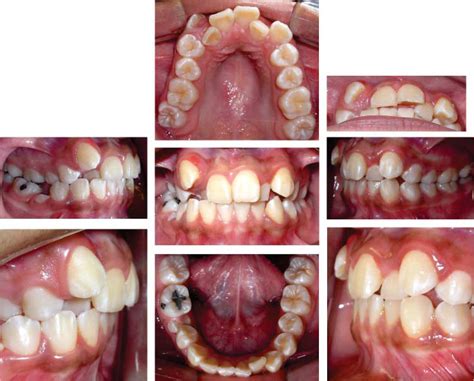

Exploración Intraoral

La paciente ya ha iniciado la segunda fase de recambio de la dentición mixta, existiendo caries oclusodistal en 64, origen de un absceso que fistuliza a este nivel por vestibular, posible caries palatina en 26 y oclusomesial a nivel de 74. Ambos primeros molares superiores presentan sendas obturaciones oclusales. La relación molar es de Clase II, completa en el lado derecho e incompleta en el lado izquierdo, estando aumentados el resalte y la sobremordida. La oclusión en relación céntrica mandibular es coincidente con la máxima intercuspidación. Existe una ligera discrepancia de líneas medias, estando la línea media inferior levemente desplazada hacia la derecha con respecto a la superior. Los incisivos superiores aparecen diastemados, intuyéndose una discrepancia oseodentaria positiva en la arcada superior, mientras que, por el contrario, la arcada inferior evidencia una clara discrepancia oseodentaria negativa (figs. 2 y 3).

Figura 2. Fotografías intraorales pretratamiento.

Figura 3. Fotografías intraorales pretratamiento. Vista oclusal.